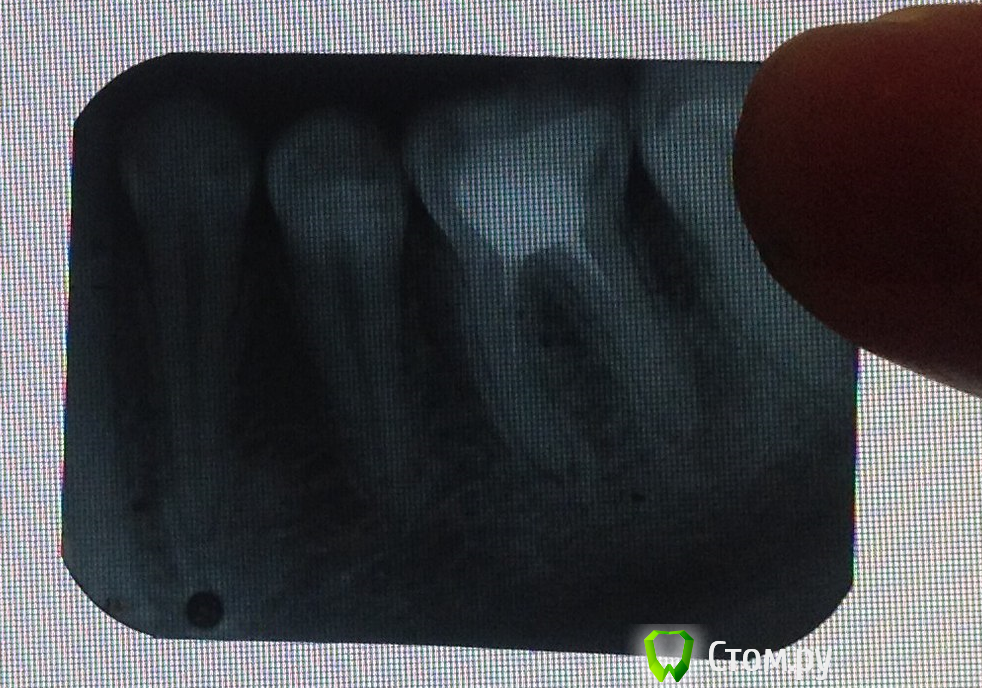

rivezico Опубликовано 18 июля, 2014 Поделиться Опубликовано 18 июля, 2014 может произойдет, а может нет определенные изменения рядом с корнями вижу, они не то чтобы критичные, но гарантии 100% никто не даст, что на отдыхе ничего не будет Ссылка на комментарий

Korel Опубликовано 18 июля, 2014 Поделиться Опубликовано 18 июля, 2014 Снимок полугодовой давности, качество не айс. На сладкое может реагировать и соседние 5 и 7. За оставшиеся 2 дня сходите на приём для консультации и сделайте ещё один снимок, может быть ничего критичного, но.... 2 Ссылка на комментарий

DokDent Опубликовано 19 июля, 2014 Поделиться Опубликовано 19 июля, 2014 спасибо всем за советы, я вам очень благодарен, болит на горячее Этот зуб на сладкое болеть не может. На горячее-да. Разберитесь с зубом до поездки. Перелёт, смена климата могут спровоцировать обострение. снимок плохой, перелечивание,скорей всего возможно,только не у того доктора,который его лечил. 1 Ссылка на комментарий